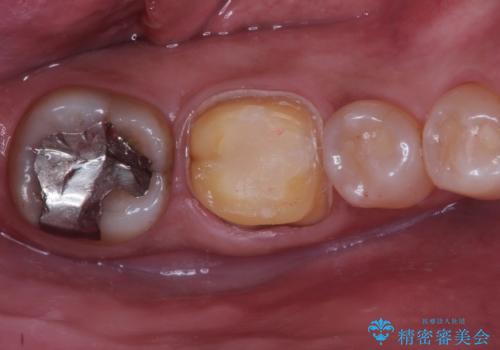

根管治療〜オールセラミッククラウン(エクセレント)の治療を行なっております。

- 精密根管治療(イニシャルケース,大臼歯):122,000円、ファイバーコア:22,000円、仮歯:11,000円、オールセラミッククラウン(エクセレント):200,000円費用は治療当時の料金となります

根管治療後の最終補綴物は予後に大きく関わります。